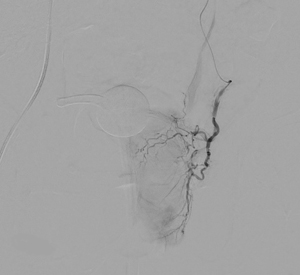

side-by-side fluoroscopic images showing pelvic vascular anatomy; the left panel displays a contrast-filled arterial tree with catheter in place, and the right panel shows a round radiopaque marker and surrounding bony structures during prostate artery embolization

picture 2Overall, the procedure involves shrinking the prostate by treating its blood vessels. An interventional radiologist gains access through a small incision in the upper thigh or the wrist. From there, small particles are injected into the prostate to slow the blood flow to the gland, causing the prostate to shrink. Relief from BPH symptoms occurs in the following weeks and months. It is a relatively painless procedure using conscious sedation. After the procedure, UCSF Radiology follows up with patients at one, six and 12 months.